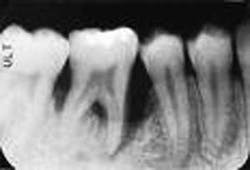

But before we discuss soft tissue invasion, I'd like to talk a little about refractory periodontitis. We've all had cases where the patient fails to respond to treatment. We do everything we can think of to stop the attachment loss, yet at each recall, the probe slides a little farther into the pockets and the radiographs look bleaker (see Figures 1 and 2).